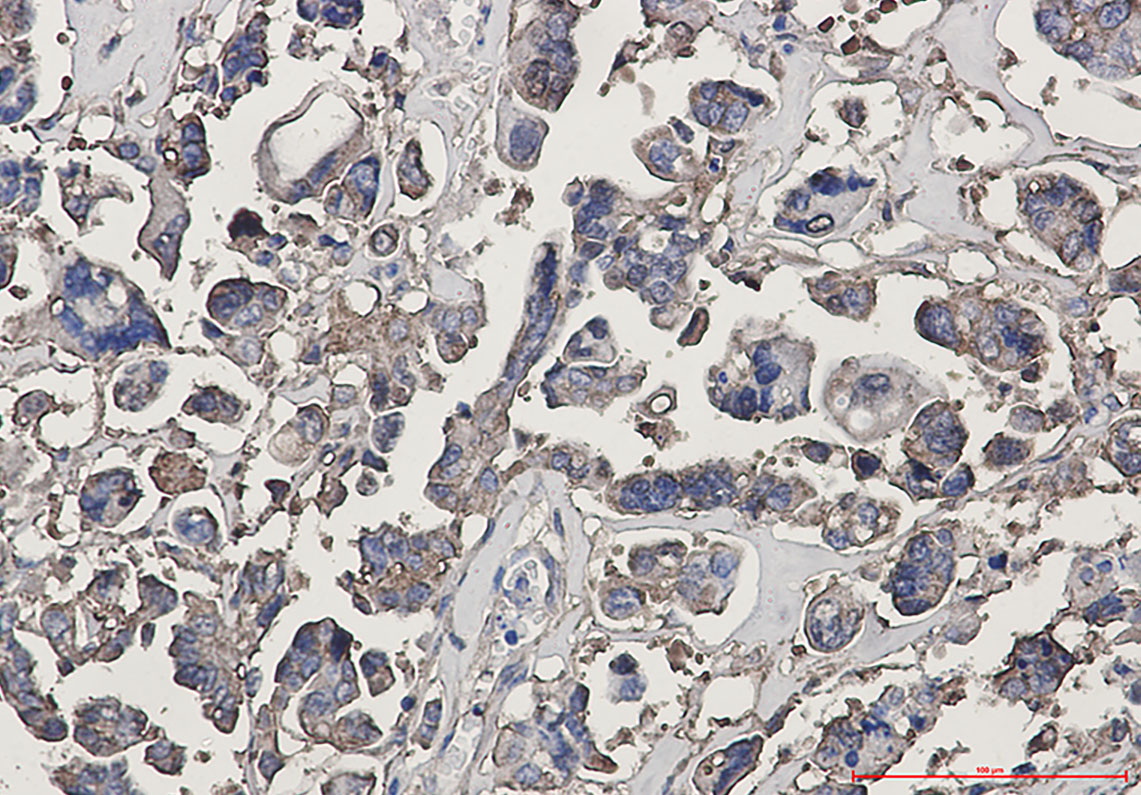

Immunohistochemistry analysis of paraffin-embedded Human Cholangiocarcinoma using beta III Tubulin antibody. High-pressure and temperature Sodium Citrate pH 6.0 was used for antigen retrieval.